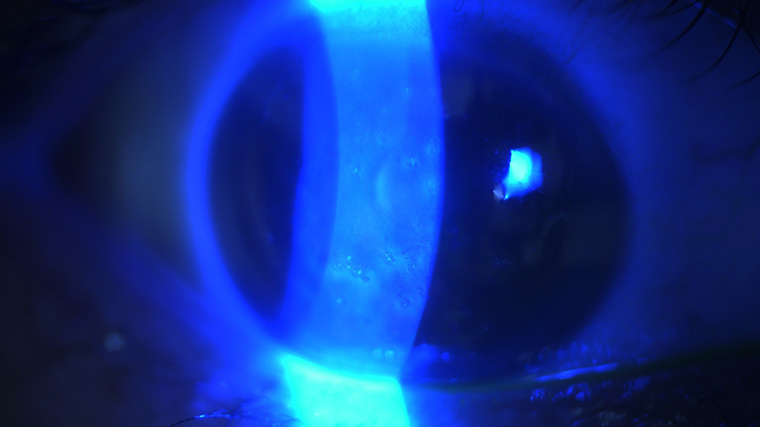

▲林育葳表示,角膜螢光染色是檢查角膜表皮細胞受損的方式之一。(圖/林育葳醫師提供)